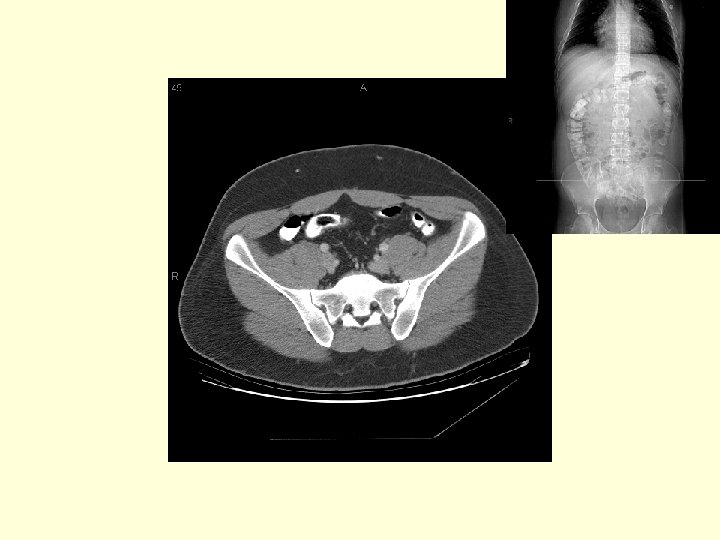

What portion of the colon is labeled with arrows? Sigmoid colon

What vascular structures are marked by the arrows? The external iliac arteries and veins